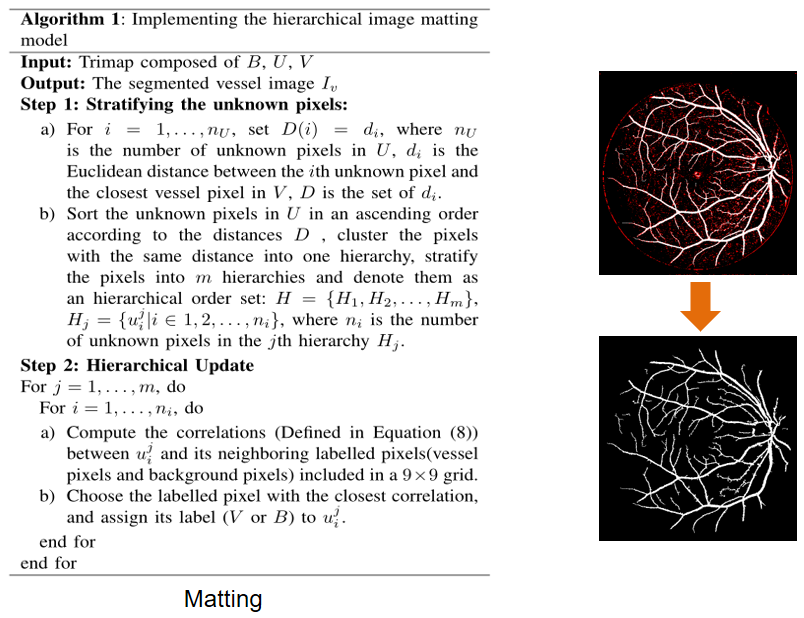

图二 三分图的生成流程和实例展示 在抠图环节提出了分层抠图模型,实现三分图的进一步分割。下面给出了分层抠图模型的算法框架和实例展示,如图三所示。该算法主要分为两步: 对未知像素点的分层(Stratifying the unknown pixels)和分层更新(Hierarchical Update)。

图三 分层抠图模型的算法框架和实例展示 图四和图五分别展示了分层抠图模型算法中两个步骤的基本流程,其中绿色代表血管点,红色代表未知点,蓝色代表背景点。在第一步对未知像素点的分层过程中,我们计算每个未知像素点与最近血管点的距离,并按该距离将未知点分层。在第二步分层更新过程中,从第一层开始,我们计算该层每个未知像素点和它最近的已知点(血管点和背景点)的关系值,选择每个未知像素点关系最近的已知点,把这个已知点的标记赋给未知的像素点。当该层所有的未知像素点更新后,我们再用它们继续对下一层的未知像素点进行更新,以此循环,直到最后一层更新完毕。